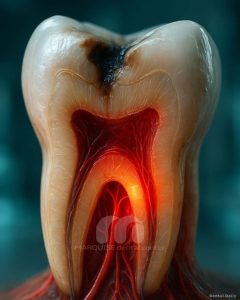

پوسیدگی دندان

پوسیدگی دندان؛ از علائم اولیه تا درمان قطعی 💎 پوسیدگی دندان یکی از شایعترین مشکلات دهان و دندان است که اگر بهموقع درمان نشود، میتواند به درد شدید، عفونت و حتی از دست رفتن دندان منجر شود. این مشکل معمولاً به دلیل تجمع پلاکهای میکروبی و عدم رعایت بهداشت دهان ایجاد میشود و در هر سنی ممکن است رخ دهد. در کلینیک دندانپزشکی مارکیز در پونک تهران، پوسیدگی دندان با روشهای دقیق و تجهیزات مدرن تشخیص داده و درمان میشود تا از پیشرفت آن جلوگیری شود. پوسیدگی دندان چیست و چگونه ایجاد میشود؟ پوسیدگی زمانی شکل میگیرد که باکتریهای دهان، قند و مواد غذایی را به اسید تبدیل میکنند. این اسیدها به مرور زمان مینای دندان را تخریب کرده و

عفونت دندان

عفونت دندان؛ راهنمای کامل پیشگیری و درمان در کلینیک دندانپزشکی مارکیز تهران عفونت دندان زمانی رخ میدهد که باکتریها به داخل پالپ دندان نفوذ کنند و باعث التهاب و درد شوند. اگر به موقع درمان نشود، میتواند به بافتهای اطراف و حتی کل بدن آسیب برساند. 😷 کلینیک دندانپزشکی مارکیز در پونک تهران، با تجهیزات مدرن و تیم حرفهای، بهترین روشهای درمان عفونت دندان را ارائه میدهد و سلامت دندان شما را حفظ میکند. علائم شایع شناسایی به موقع علائم عفونت دندان اهمیت زیادی دارد. برخی از رایجترین علائم عبارتاند از: درد شدید و مداوم دندان، به ویژه هنگام جویدن تورم و قرمزی لثه اطراف دندان حساسیت بیش از حد به دماهای گرم و سرد بوی بد دهان و طعم